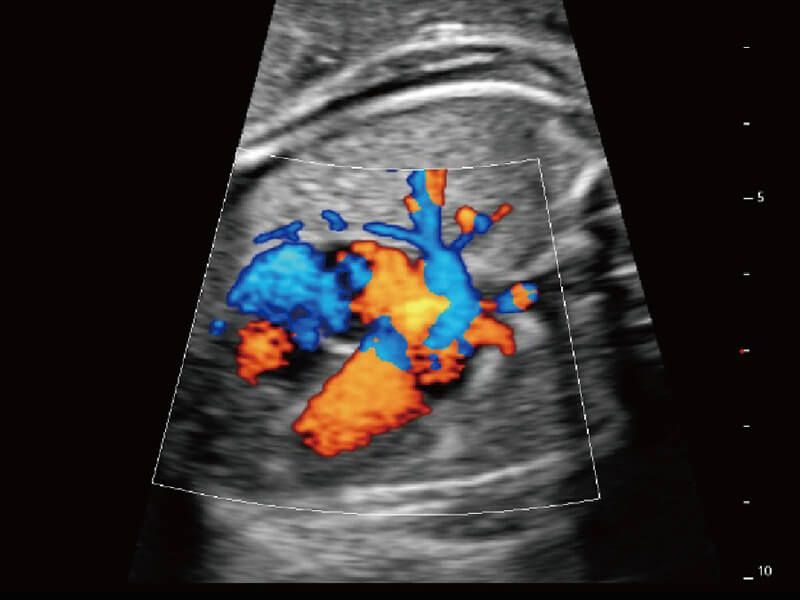

性能优异的硬件架构,极大提升超声系统的运行效率和数据处理能力。相比以往超声成像系统,Wis+平台为您带来极快的响应速度和成像帧频,提升检查流畅度。

S60探头工艺,从前端信号处理每一个环节采集无损声学数据,真实还原组织原貌,再现解剖细节。